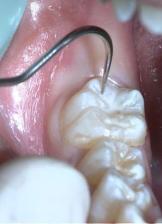

1.清洁牙面: 用装有毛刷的低速手机蘸适量浮石粉或不含氟的牙膏刷洗牙面后彻底冲洗,再用探诊清除窝沟中残留的清洁剂。

6.检查: 封闭剂固化后,用探针进行全面检查。检查固化程度,有无气泡存在,寻找遗漏或未封闭的窝沟,观察有无过多封闭材料和是否需要去除,如发现问题应及时处理。